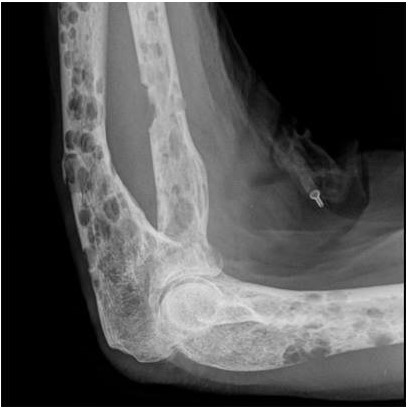

Một số bệnh ác tính cũng gây ra tình trạng loãng xương:

- Đa u tủy xương

- Ung thư di căn xương

Bệnh đa u tủy xương